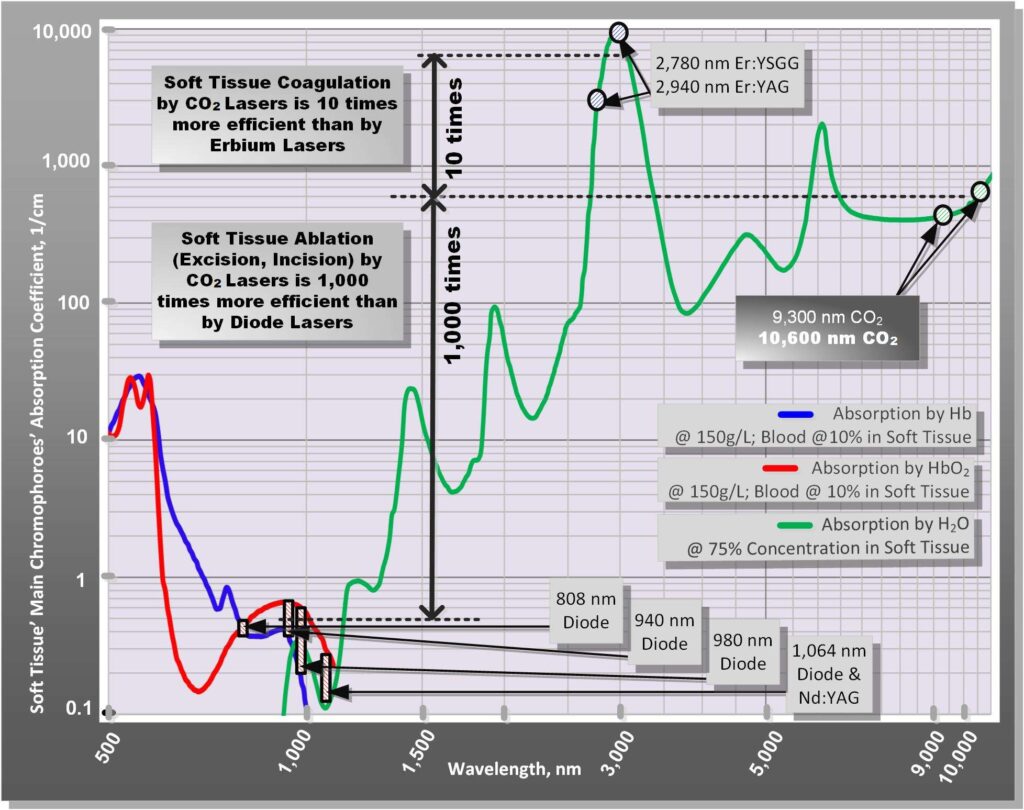

Not all lasers are equally efficient at both tissue vaporization (i.e., ablation or cutting) and coagulation. The difference is illustrated in the absorption spectra for main soft tissue chromophores[28,29] in Figure 4. Some dental laser wavelengths (around 3,000 nm, such as Erbium lasers) are well absorbed by the water-rich soft tissue and are great at cutting but are not as efficient at coagulating.[29] Other dental laser wavelengths (around 1,000 nm, such as diodes and Nd:YAG) are efficient coagulators, but inefficient scalpels[30] since they are poorly absorbed by the soft tissue.

The 10.6 micrometers CO2 laser wavelength is efficient at both vaporizing and coagulating the soft tissue simultaneously (Figure 4), although it is not as good as Erbium laser at cutting and not as good as diode/Nd:YAG at coagulating. Most importantly, the CO2 laser’s coagulation depth closely matches the blood capillary diameters,[29] as illustrated in Figure 5.